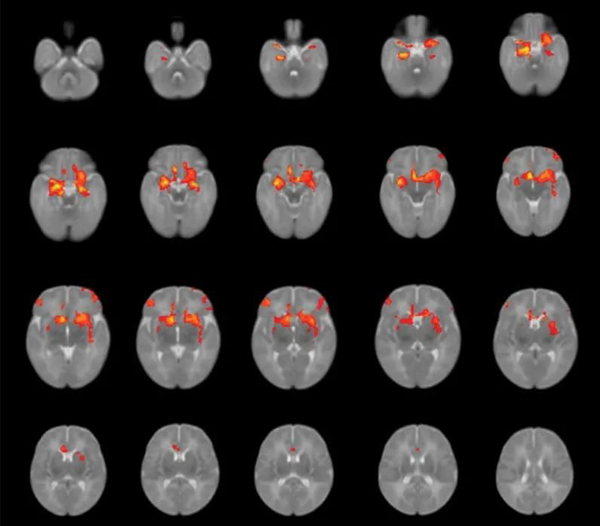

At the same time, the enormous stress the mother experiences during pregnancy may be a major factor that negatively affects the brain development of the fetus.

Researchers at the University of Calgary in Canada surveyed more than 8,000 pregnant women during the outbreak. Nearly half reported symptoms of anxiety, and one-third had symptoms of depression — a much higher rate than in the years prior to the outbreak of Covid-19.